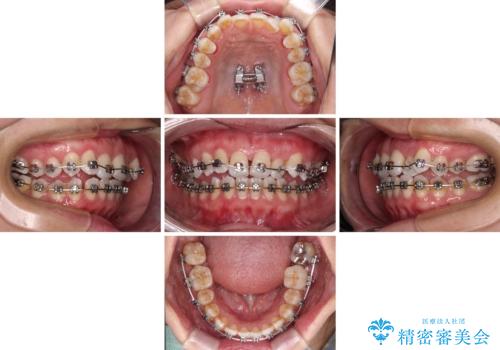

- 全顎的なクロスバイトと反対咬合を気にして来院された患者様です。

骨格的に下顎が前方位にありましたが、歯並びにより下顎が本来の位置よりも前方位に誘導される咬み合わせとなっていました。

上顎歯列および上顎骨が下顎に対して狭小であることが原因であるため、上顎の急速拡大装置を使用して上顎骨を側方に拡大することで反対咬合を改善し、ワイヤー装置で歯列を整えることとしました。

上顎の拡大に伴い反対咬合があっという間に改善されました。

元々の歯列不整は軽微であったため、僅か1年の期間で治療を終えることができました。